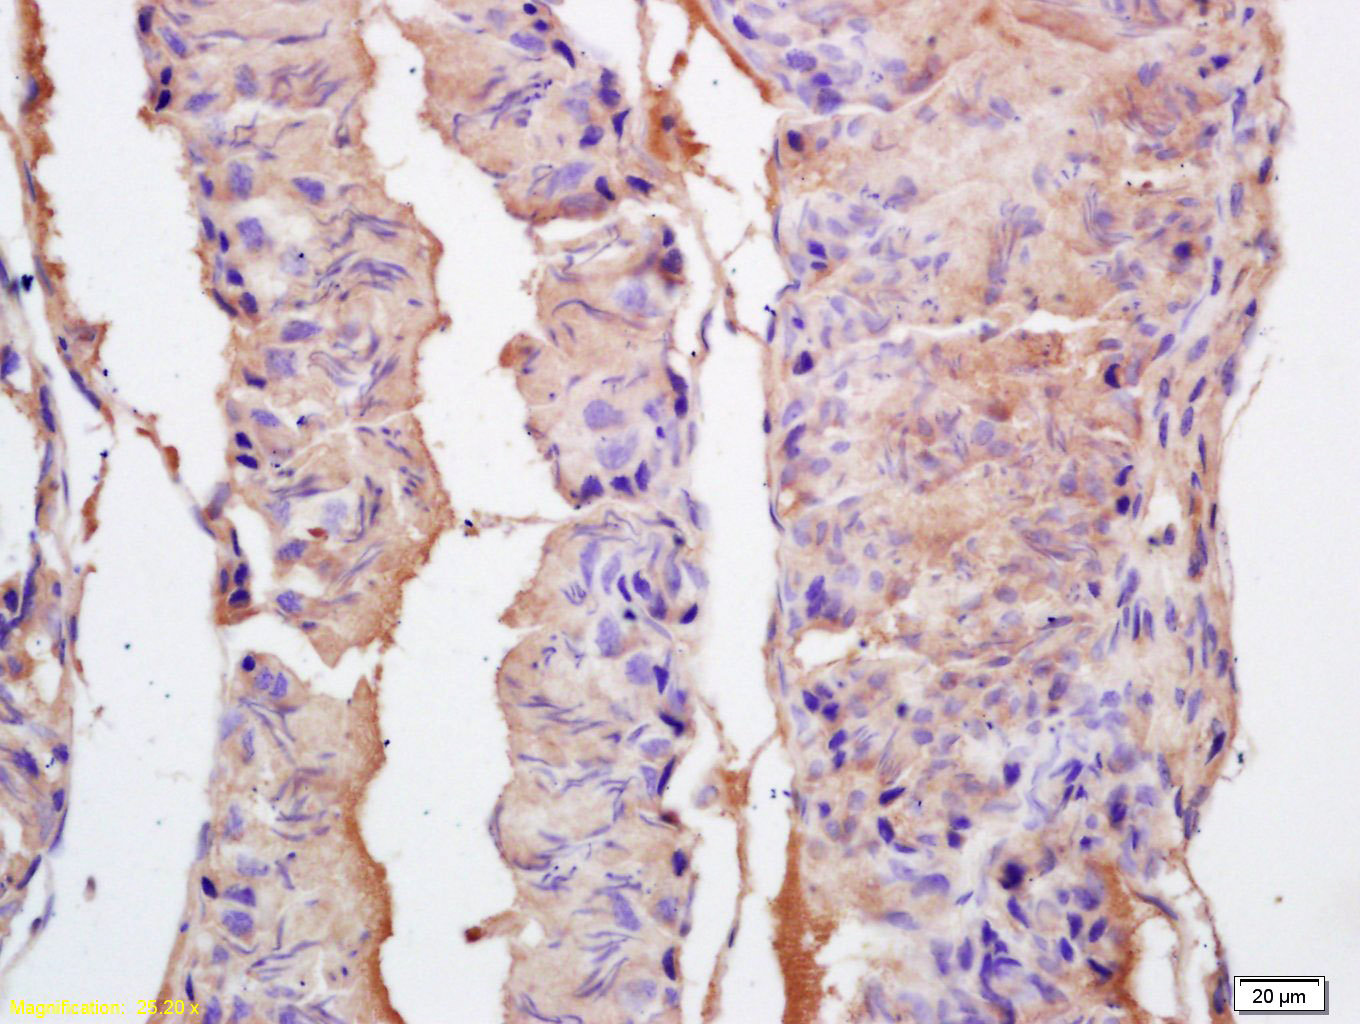

Tissue/cell: rat testis tissue; 4% Paraformaldehyde-fixed and paraffin-embedded; Antigen retrieval: citrate buffer ( 0.01M, pH 6.0 ), Boiling bathing for 15min; Block endogenous peroxidase by 3% Hydrogen peroxide for 30min; Blocking buffer (normal goat serum,C-0005) at 37℃ for 20 min; Incubation: Anti-EPHA10 Polyclonal Antibody, Unconjugated(bs-10052R) 1:200, overnight at 4°C, followed by conjugation to the secondary antibody(SP-0023) and DAB(C-0010) staining